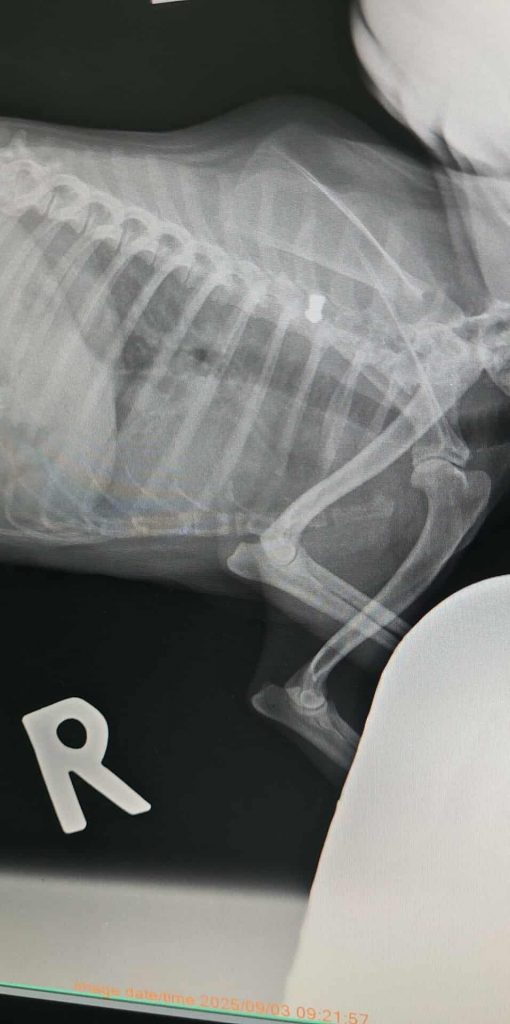

Pukule war in einem Zwinger auf dem Gelände einer ehemaligen Ziegelei im Bezirk Alytus eingesperrt. Das Unternehmen ist schon lange nicht mehr aktiv, aber irgendwann hatten sich dort etwa 18 Hunde angesammelt, die die Leute zu vergiften begannen. Eine in der Nähe wohnende Oma hatte Mitleid mit den Hunden und sperrte Pūkulė und ein anderes Mädchen in den Zwinger und fütterte sie. Das Tierheim brachten sie in die Klinik, weil sie beim Abholen stark hustete. Nach einer Röntgenuntersuchung, um sicherzustellen, dass ihre Lungen gesund sind, wurde eine seit langem darin steckende Kugel entdeckt.

Bei der Untersuchung beim Tierarzt sind keine Herzgeräusche oder Pfeifgeräusche zu hören. Im Moment hustet sie nicht. Der Arzt meint, dass sie vielleicht wegen Stress hustet und hat ihr Medikamente verschrieben – sie kommt bald wieder zur Untersuchung in die Klinik.